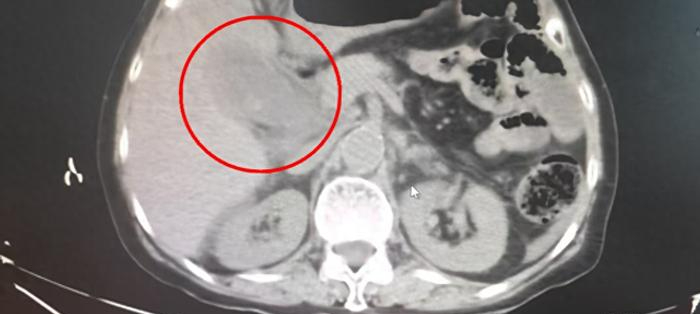

Một phụ nữ 40 tuổi ở Phúc Kiến có 95 viên sỏi mật trong túi mật vì cô ấy đã bỏ bữa sáng trong một thời gian dài và có thói quen ăn vặt vào đêm khuya. Ngay cả các bác sĩ cũng bị sốc khi họ lấy ra những viên sỏi này. Các bác sĩ chỉ ra rằng, việc bỏ bữa sáng trong thời gian dài sẽ dẫn đến tình trạng ứ mật, hình thành sỏi, có thể gây tắc mật hoặc viêm tụy cấp, vô cùng nguy hiểm.

Câu chuyện của người phụ nữ tên Trương đến từ Phúc Kiến (Trung Quốc) này được đăng trên tờ Guangzhou Daily. Cô thường xuyên cảm thấy khó chịu ở bụng và phải đến gặp bác sĩ. Sau đó, bác sĩ đã lấy ra tới 95 viên sởi từ túi mật của cô.

Bác sĩ trưởng khoa Phẫu thuật gan mật, tụy và lách điều trị cho cô Trương đã vô cùng bất ngờ khi thấy nhiều sỏi như vậy. Ông cho biết, trường hợp như vậy tương đối hiếm gặp và cực kỳ nguy hiểm. Nó giống như một quả bóng nước chứa đầy sỏi, có thể gây tắc ống mật hoặc viêm tụy cấp bất cứ lúc nào.